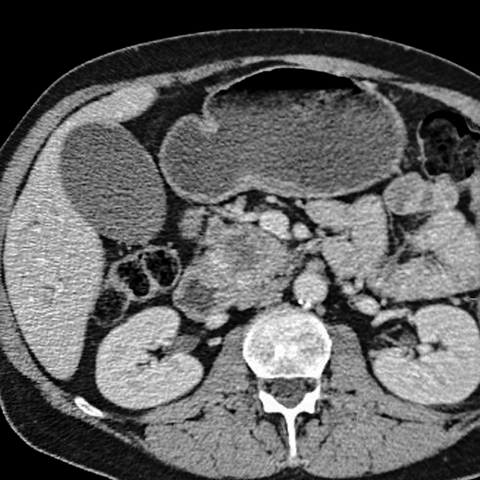

56 year-old male with painless jaundice [3 of 4]